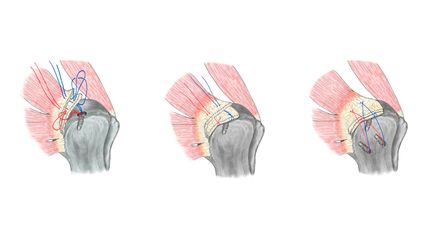

Entsprechend konnte gezeigt werden, dass die kombinierte Korrektur von Varus und tibialem Slope unter axialer Belastung zu einer deutlichen Reduktion der VKB-Transplantatkräfte – in experimentellen Modellen um bis zu 58% – führt.35 In Revisionssituationen mit varischer Beinachse und gleichzeitig steilem tibialem Slope stellt daher eine biplanare Osteotomie mit kombinierter Varus- und Slope-Korrektur, ergänzt durch eine simultane oder zweizeitige VKB-Rekonstruktion, die biomechanisch sinnvollste Strategie dar.23,50 Der Einsatz patientenspezifischer Instrumente (PSI) kann dabei die Präzision der kombinierten Varus- und Slope-Korrektur erhöhen und ist eine sinnvolle Unterstützung der präoperativen Planung sowie der intraoperativen Umsetzung (Abb. 3).